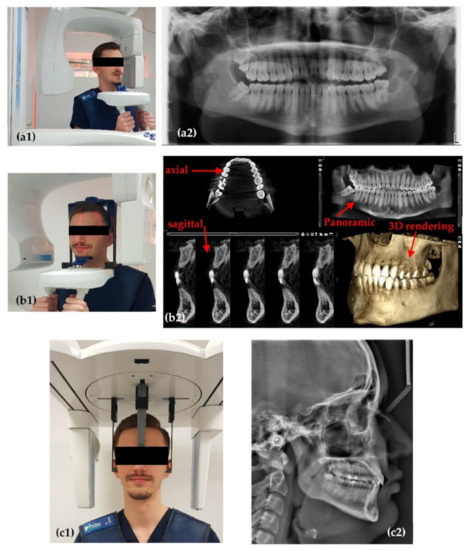

2.1. Planmeca ProMax 3D

2.2. Soredex Cranex 3D

2.3. OCT System